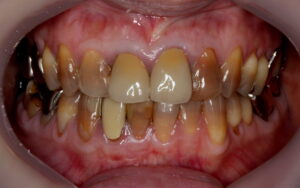

こちらはテトラサイクリン歯の1例です。

歯の1~2本だけでなく全体的な変色があるケースで審美的にマイナスになりがちです。

こちら、テトラサイクリン歯と失活歯と古いクラウンの症例となっております。

術前 削らないラミネートベニア4本

+クラウン2本

全体的にはホワイトニングを行っています。

テトラサイクリン歯 と 左上2や右下1などの失活歯 にもホワイトニング効果は出ています。